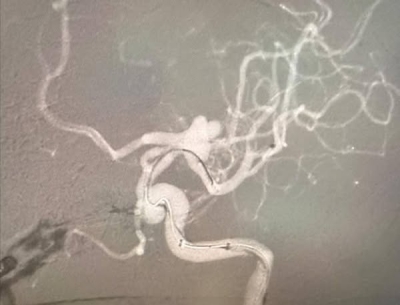

وخلال العملية، تم تركيب شبكة دقيقة بين الشريان الدماغي الأوسط والشريان السباتي الداخلي، ما ساعد على تحويل مسار الدم بعيدًا عن الكيس الدموي المنفجر، وبالتالي وقف النزيف بشكل كامل .

ومن جانبه، أكد الأستاذ الدكتور محمد أبو جاموس أن سرعة التشخيص والتدخل الفوري كان لهما الدور الأساسي في إنقاذ حياة المريض ومنع حدوث مضاعفات عصبية خطيرة، مشيدًا بروح التعاون والعمل الجماعي بين تخصصي جراحة الأعصاب والأشعة التداخلية .

وغادر المريض المستشفى وهو يتمتع بصحة تامة ودون أي مضاعفات تُذكر.